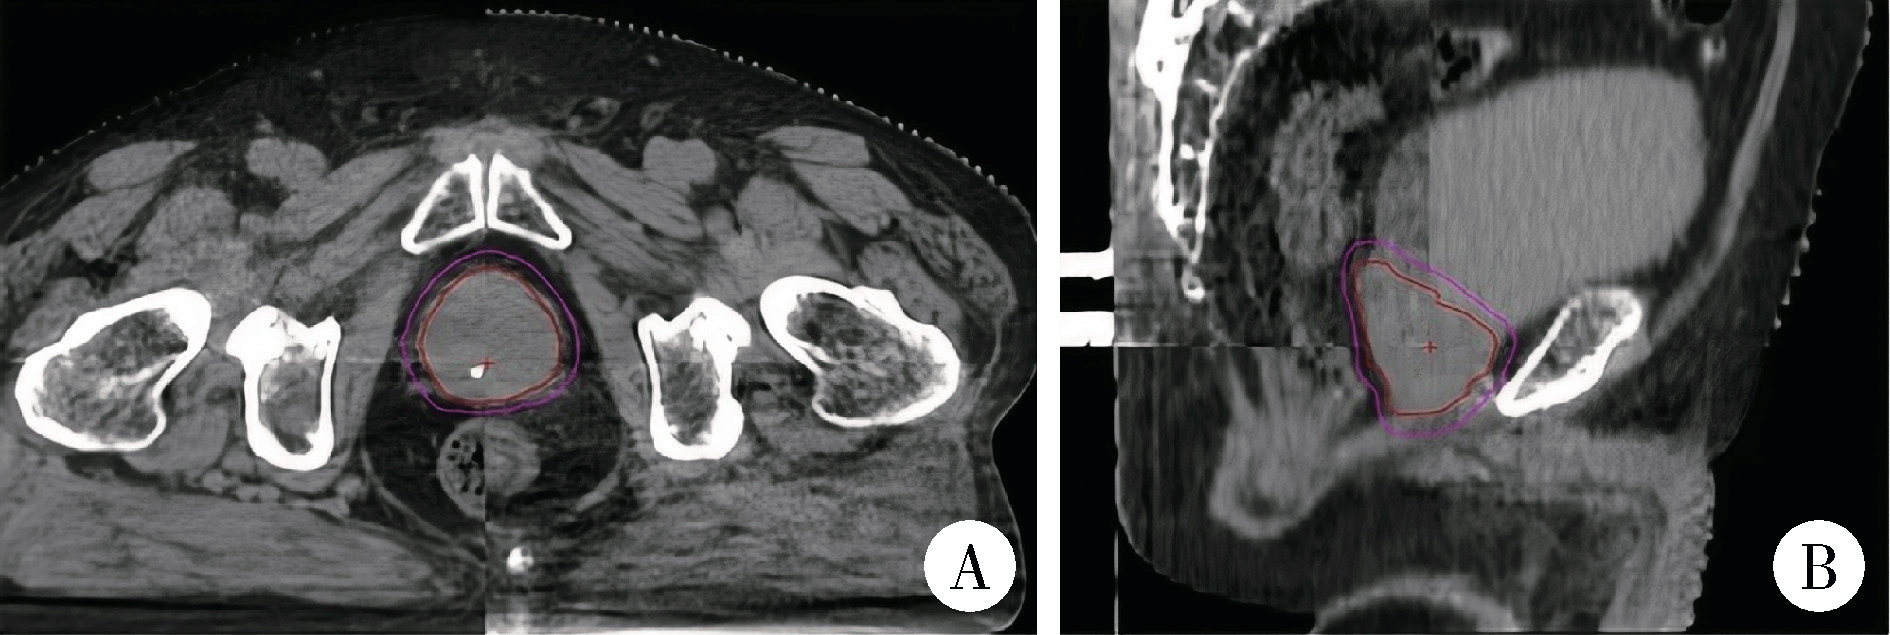

Comparison of setup errors between two immobilization methods in prostate cancer radiotherapy based on cone-beam computed tomography

- Department of Radiation Oncology, Peking University First Hospital, Beijing 100034, China